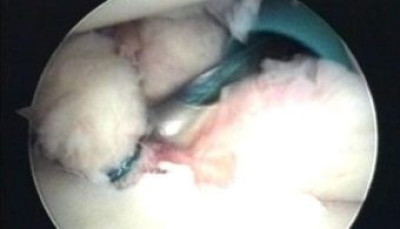

Se está realizando la anudación con la ayuda de un instrumento metálico (knot pusher)